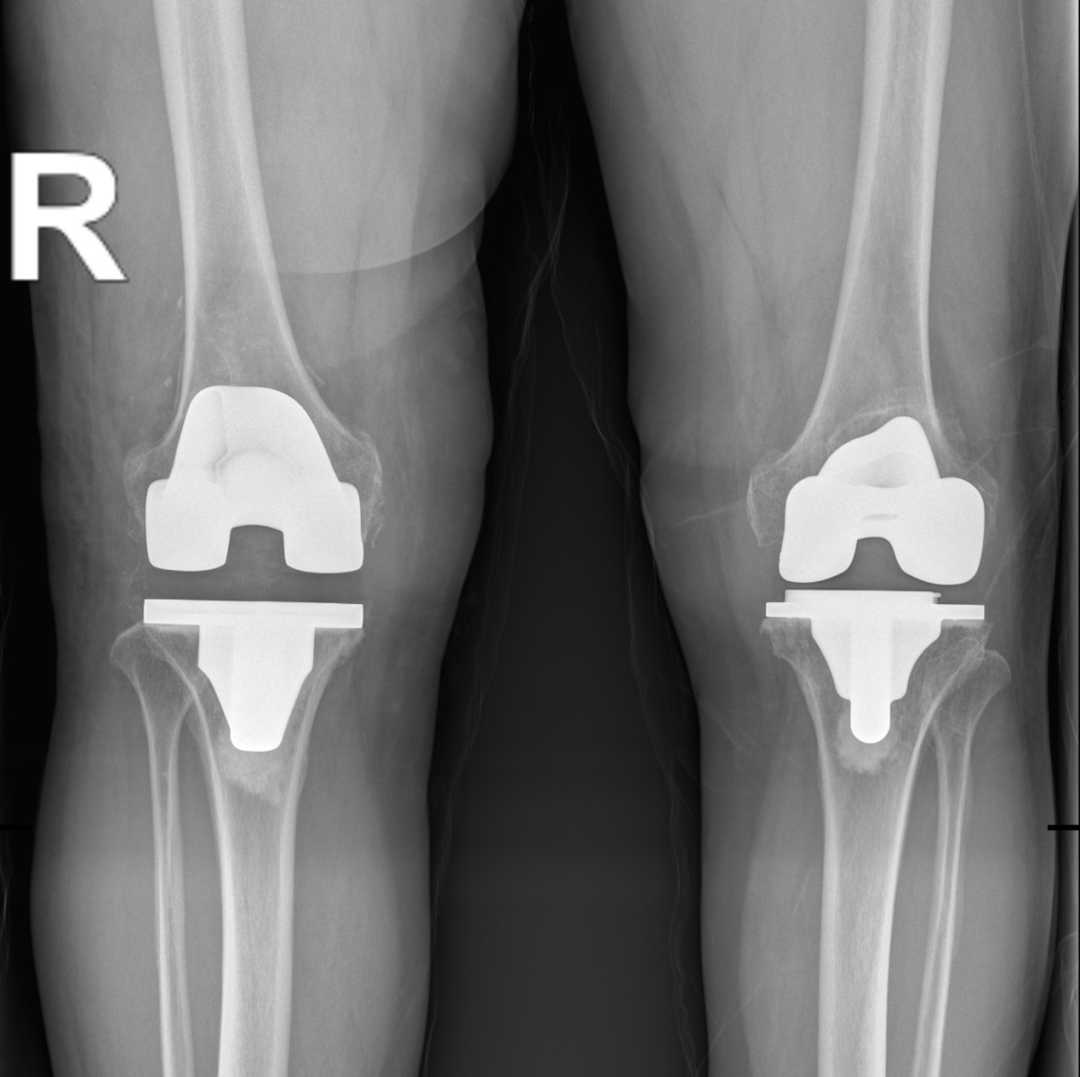

第一次左侧人工全膝关节置换术后